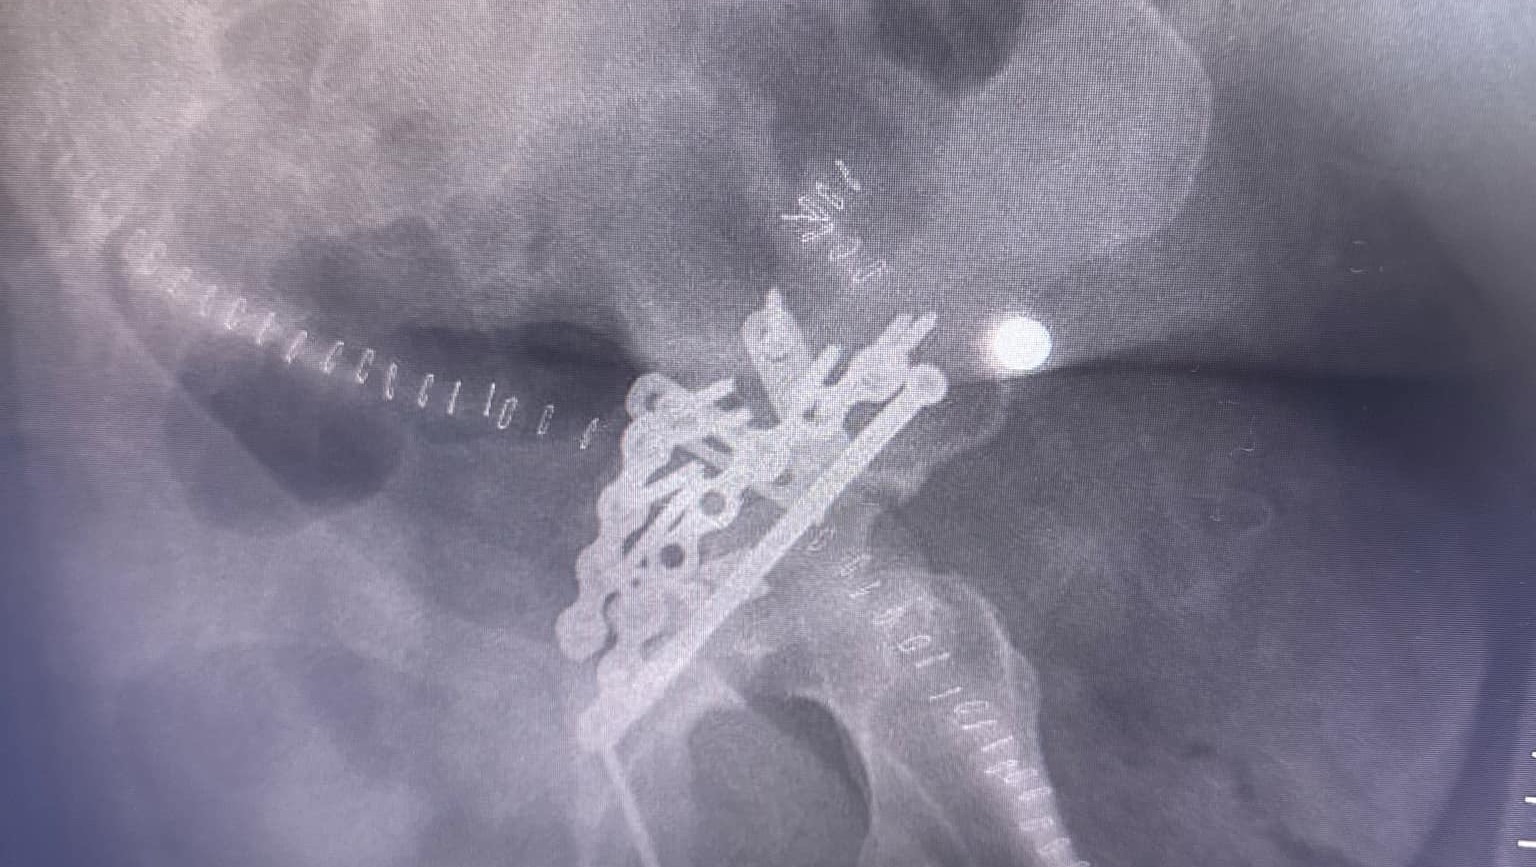

Tyler broke his Hip, Elbow, (bone is sticking out ) and he Broke his vertebrae T7-T11

he has had his surgeries on his spine, hip and elbow.